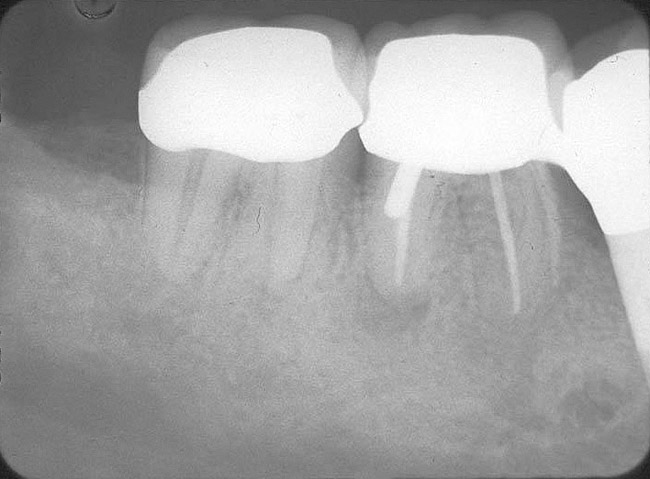

3. Extraction of a hopeless mandibular molar, defect debridement, and placement of an implant in one of the root sockets, followed by restoration with a molar-sized crown. This approach addresses the concern of two implants being placed closely together in the root extraction sockets. However, this treatment appropriately results in a mesial cantilever of the implant restoration and an area of potential plaque accumulation (Figure 1).

Figure 1  An implant has been placed in the mesial root socket at the time of mandibular molar extraction. The subsequent restoration demonstrates a significant cantilever and is not conducive to effective home care efforts.

Figure 1